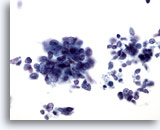

画像 4

肝FNA – 良性肝細胞

反応性変化を来した肝細胞。核は大小不同で、二核を有しています。

40倍

画像 4

肝FNA – 良性肝細胞

反応性変化を来した肝細胞。核は大小不同で、二核を有しています。

40倍